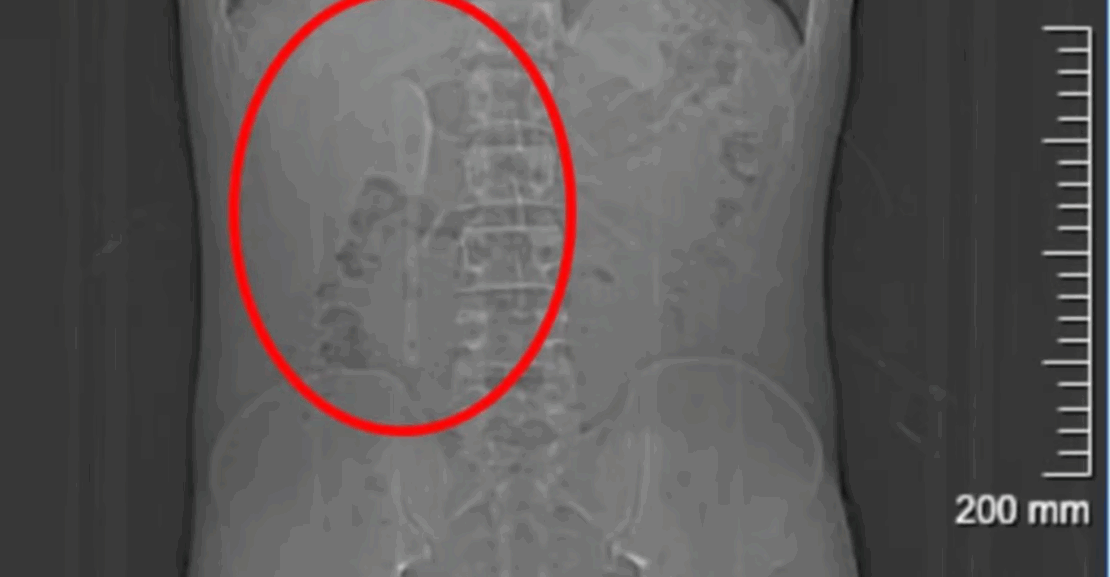

No entanto, ao procurar atendimento médico em Xangai, na China, ele descobriu que o objeto estava realmente alojado em seu duodeno, a primeira parte do intestino delgado.

Durante os cinco meses seguintes, Yan continuou sua rotina normalmente e até praticava exercícios físicos sem apresentar sintomas graves. Só em junho, ao desconfiar que poderia ter ingerido algum plástico junto com comida de delivery, procurou um hospital em Xangai, onde exames revelaram a colher de 15 centímetros presa em uma posição delicada dentro do duodeno.

Os médicos explicaram que a extração seria difícil devido à superfície lisa da colher e à localização que colocava o intestino em risco de perfuração, podendo causar inflamação ou hemorragia intensa. A cirurgia endoscópica durou cerca de nove horas e envolveu o uso combinado de dois tipos de pinças para puxar a colher de volta ao estômago e, em seguida, removê-la.